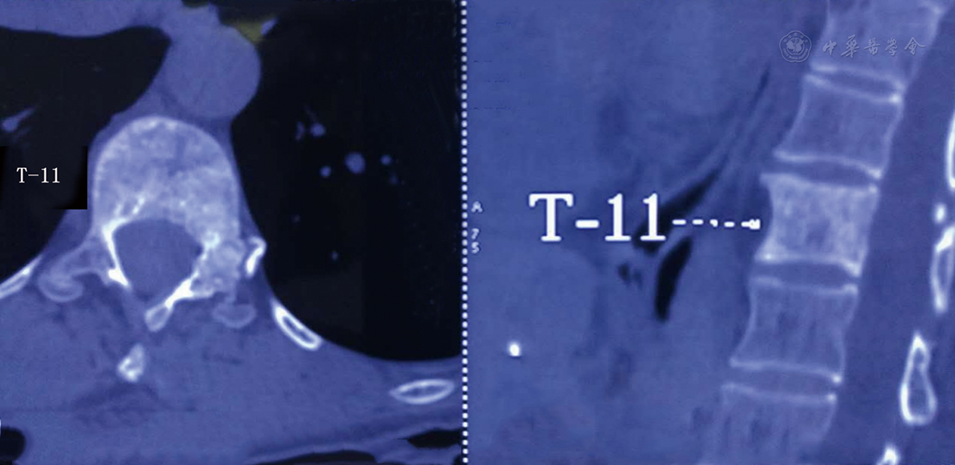

PET-CT检查示T11椎体及左侧椎体骨质密度不均匀性增高,未见明显的FDG异常摄取,提示良性病变可能大(病例91图1)。